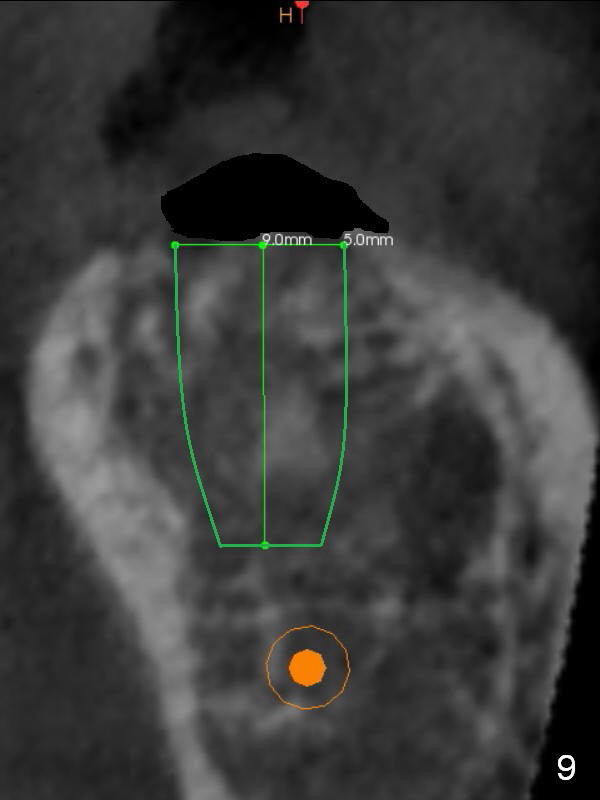

To bury the implant evenly, the ridge should be flattened (Fig.8) prior to osteotomy and implant placement (Fig.9) when bone height is sufficient.